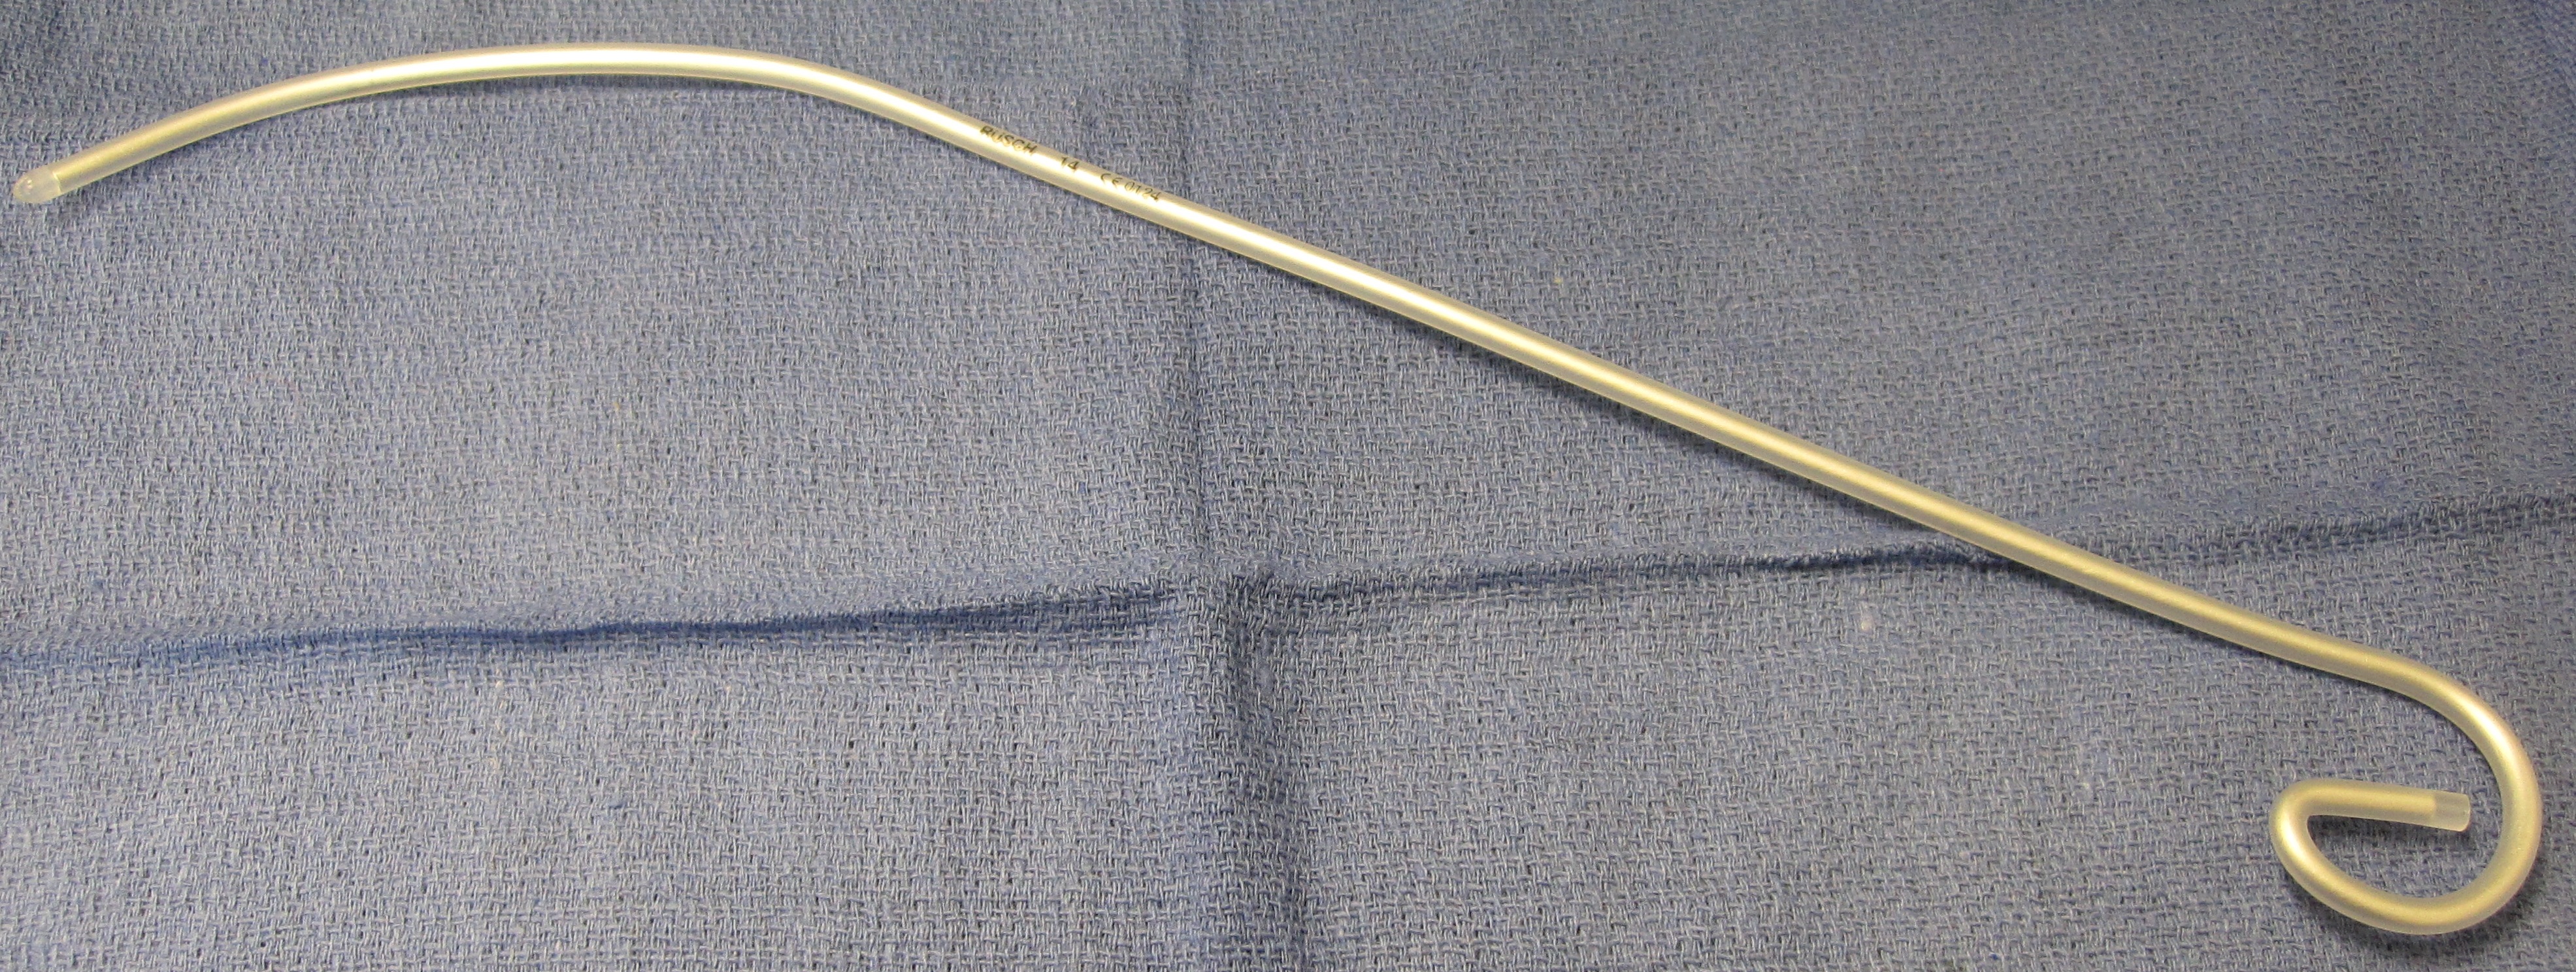

에쉬만 기관 튜브 삽입기( "검 엘라스틱 부지"라고도 함)는 어려운 기관 삽관을 용이하게 하기 위해 사용되는 특수 유형의 스타일렛이다. 이 유연한 장치는 길이가 60cm이며, 프렌치 15(5 mm 직경)이고 먼 끝에 작은 "하키 스틱" 각도가 있다. 일반적인 기관 삽관용 스타일렛과 달리, 에쉬만 기관 튜브 삽입기는 일반적으로 기관에 직접 삽입된 다음 기관 내 튜브를 통과시키는 가이드로 사용된다 (젤딩거 테크닉과 유사한 방식).